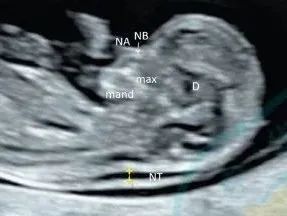

NT检查

测量胎儿颈项透明层厚度,可以早期筛查胎儿染色体疾病和早期发现多种原因造成的胎儿异常,如果NT指标异常要行产前诊断。